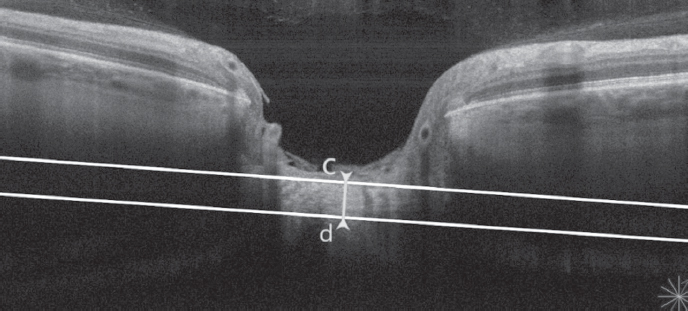

In all subjects, TLC and DLC were measured using the OCT RS-3000 Advance (Nidek, Japan) in an enhanced depth imaging mode, using the DISC RADIAL protocol and calculating the average value of these parameters from three consecutive measurements. DLC (posterior LC displacement) was defined as the perpendicular straight line drawn between the center of this line and the front surface of the LC (a–b). TLC was defined as the segment between the anterior and posterior surfaces of the LC in its central part (c–d) (Fig. 1, 2). To measure the LC parameters, a line connecting the end points of the Bruch’s membrane was used as a base plane. The same OCT device was used to measure the central thickness of the cornea using a nozzle for the anterior segment of the eye. It was additionally measured using a Pentacam HR device (Oculus, Germany).

Fig. 2. Lamina cribrosa thickness measurement (c–d) by EDI (Enhanced Depth Imaging) mode of Nidek RS-3000 Advance

Рис. 2. Измерение толщины решётчатой пластинки (c–d) с помощью оптического когерентного томографа Nidek RS-3000 Advance в режиме увеличенной глубины изображения (EDI)